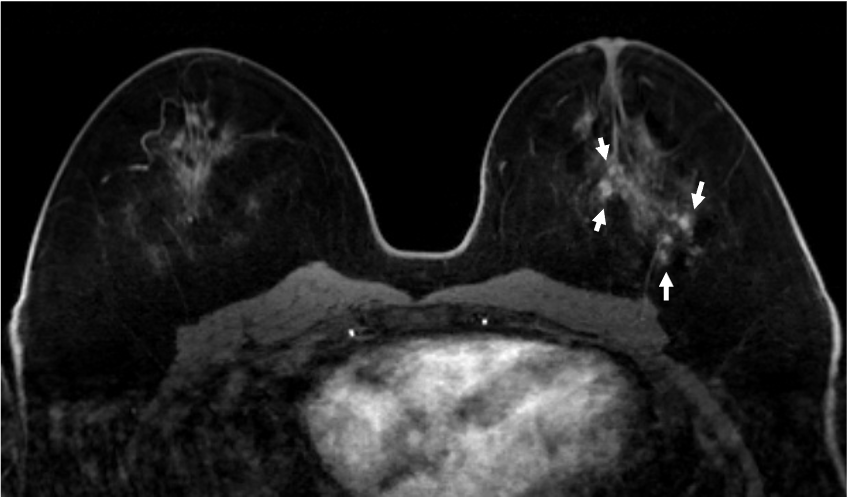

4. ダイナミックMRI (造影前 早期相 遅延相)

乳腺散在性の乳房であるが、造影早期から背景乳腺の大部分が造影されており、BPEはmarkedである。DCISの病変(矢印)は、clumped、segmental distributionの腫瘤非形成性病変(Non-mass enhancement)を示しているが、BPEが強く、広がり診断が困難である。